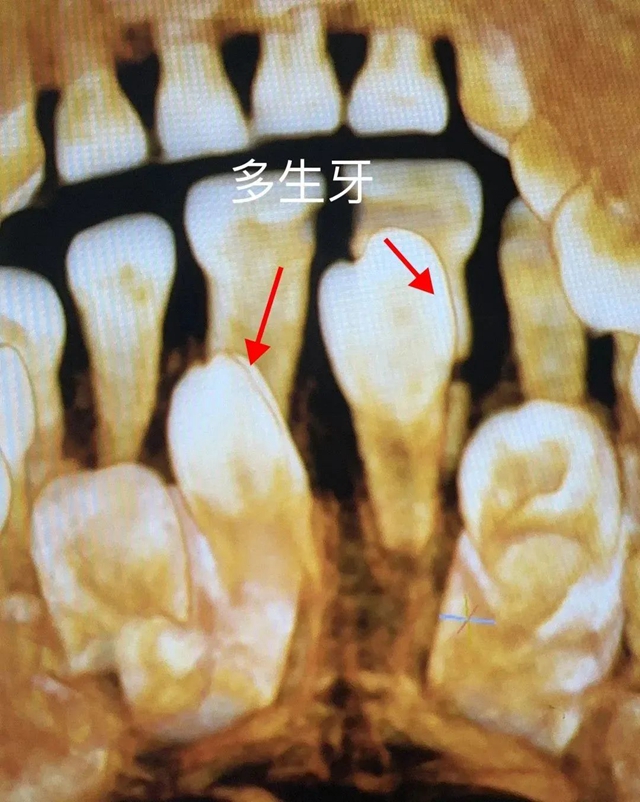

近日,医院口腔科接诊了一位4岁半的小朋友,其上前牙腭侧萌出一颗牙,经CT检查,发现小朋友的上颌两颗中切牙腭侧有两颗多生牙,一颗已萌出并导致其中一颗乳牙牙根被压迫吸收折断并唇向移位,另一颗埋伏阻生,且两颗多生牙占据了恒中切牙牙胚的正常萌出位置。

李颂经详细口内检查,并结合小朋友CT,建议拔除腭侧多生牙及松动乳牙,给恒牙留出足够的萌出通道。但基于小朋友年纪小、配合度差,局麻下拔除会对患儿身心造成影响,李颂联合麻醉科会诊综合评估后,建议在全麻下行无痛拔牙。